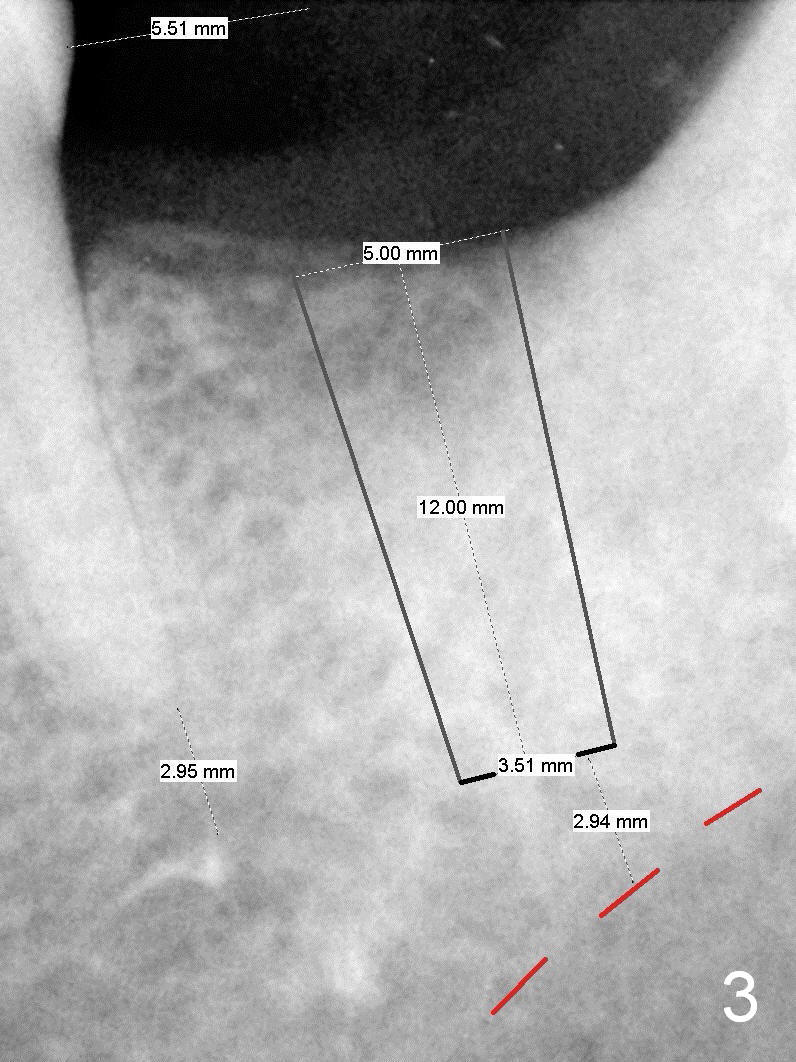

A 48-year-old lady is a dental phobic, requesting extraction of the lower left 2nd molar (Fig.1). She returns for implant placement 9 months post extraction (Fig.2). The ridge is mildly to moderately atrophic. It appears that a 5x12 mm implant is appropriate for the site (Fig.3). For safety, osteotomy is initiated at the depth of 10 mm; it appears that there is enough height for a 12 mm implant (Fig.4). The depth is controlled by drill stopper (Fig.5 S). Finally a 5x12 mm implant is apparently safely placed (Fig.6). A healing abutment is placed and the incision is sutured with 4-0 Chromic gut (Fig.7). Perio dressing is applied around the healing abutment for wound protection (Fig.8). It appears that the healing abutment (Fig.8': *) helps stabilize the perio dressing, which remains in place 1 week postop. When the perio dressing is removed, the wound around the healing abutment is healing (Fig.9). There is no bone loss around the implant 3 months postop (Fig.10 (H: healing abutment), or 16 months postop (i.e., 9 months post cementation, Fig.11,12). The patient complains of pain when she chews with the implant crown, but pain stops whenever she does not bite. Percussion does not elicit any discomfort. The gingiva is healthy. There is possibility of the buccal plate being thin or the lingual plate being perforated in the submandibular fossa. If the discomfort remains the same next 6 months, CBCT will be prescribed.